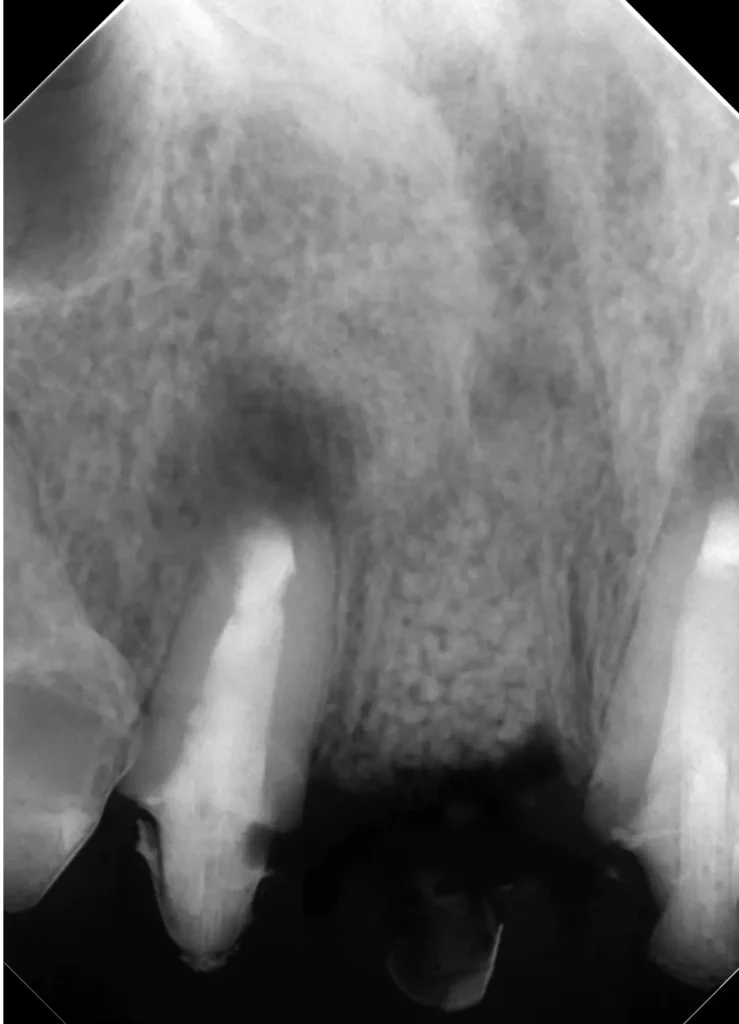

自費根管治療症例1 治療前

左上の奥歯の腫れと噛んだ時の痛みで来院。

レントゲン写真

根の先にうみが溜まっています